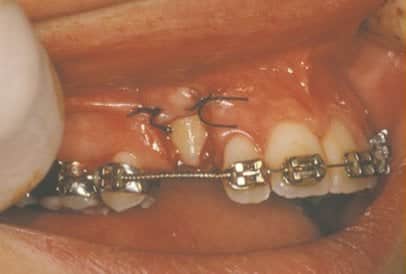

In cases where the eyeteeth will not erupt spontaneously, the orthodontist and oral surgeon will work together to get these teeth to erupt. Each case must be evaluated on an individual basis, but treatment will usually involve a combined effort between the orthodontist and the oral surgeon. The oral surgeon will expose and bracket the impacted eyetooth.

The goal is to erupt the impacted tooth and not to extract it. Once the tooth has moved into its final position, the gum around it will be evaluated. In some circumstances, there may be some minor “gum surgery” required.

The surgery to expose and bracket an impacted tooth is a very straightforward surgical procedure that is performed in the oral surgeon’s office. For most patients, it is performed using laughing gas and local anesthesia. In selected cases it will be performed under IV sedation if the patient desires to be asleep, but this is generally not necessary for this procedure. If the procedure only requires exposing the tooth with no bracketing, the time required will be shortened by about one half. These issues will be discussed in detail at your preoperative consultation with your doctor.